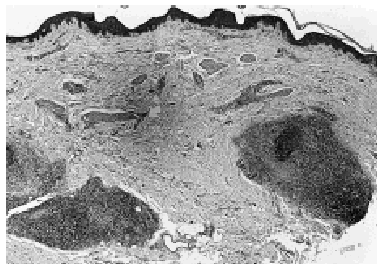

Fig. 2.--Imagen panorámica donde se observa un infiltrado linfoide denso, exclusivamente alrededor de los folículos pilosos (hematoxilina-eosina).